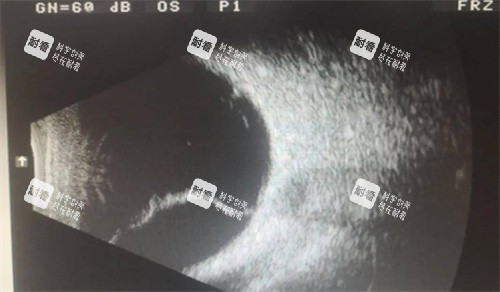

視網(wǎng)膜脫落是一種重的影響視力的眼部疾病,通常需要通過手術(shù)進行治療。許多患者在面臨視網(wǎng)膜脫落手術(shù)時,都會關(guān)心手術(shù)的費用問題。本文將詳細為大家介紹視網(wǎng)膜脫落手術(shù)的收費情況。

術(shù)前需要進行一系列的檢查,如眼部超聲、眼底照相、眼壓測量等,以確定視網(wǎng)膜脫落的情況和患者的眼部整體狀況。這些檢查費用大約在 1000 - 2000 元左右。

除了與鞏膜扣帶術(shù)相同的檢查項目外,可能還需要進行一些更詳細的檢查,如光學(xué)相干斷層掃描(OCT)等,以更比較準(zhǔn)地了解視網(wǎng)膜的情況。術(shù)前檢查費大約在 1500 - 2500 元左右。